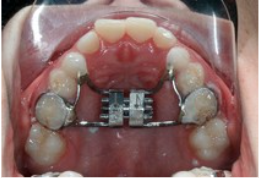

2. Skeletálně kotvený hyrax

• Stejný princip expanze, ale tlak síly na patrový šev není veden přes zuby, ale přímo na patrové kosti. Tím odpadá riziko vyklonění postranních zubů mimo kost a vznik krčkových defektů v této oblasti. Indikovaný od 12 let. Přibližně od tohoto věku je patrový šev "tuhý" a síla vedená přes zuby by vyklonila zuby (někdy až mimo kost-riziko vzniku odhalených krčků a další s tím spojené problémy parodontu) a patro jako takové by zůstalo úzké.

Skeletální hyrax je typ rychlošroubového patrového expandéru, který se používá k rozšíření horní čelisti u pacientů s těžší transverzální nedostatečností. Na rozdíl od klasického hyraxu, který je fixován na zubech, je skeletální hyrax kotven přímo do kosti horní čelisti pomocí miniimplantátů (tzv. MARPE – Miniscrew-Assisted Rapid Palatal Expansion). Tento způsob léčby je efektivní zejména u dospívajících a dospělých pacientů, kde již nelze dosáhnout expanze pouze dentálně.

• Hyrax se upevňuje na čtyři miniimplantáty, které jsou zavedeny do patrové kosti.

• Celý zákrok trvá přibližně 30 minut. Lze zavádět v celkové anestezii, zvláště při nutnosti osteotomií (narušení kostí pro výraznější expanzi).